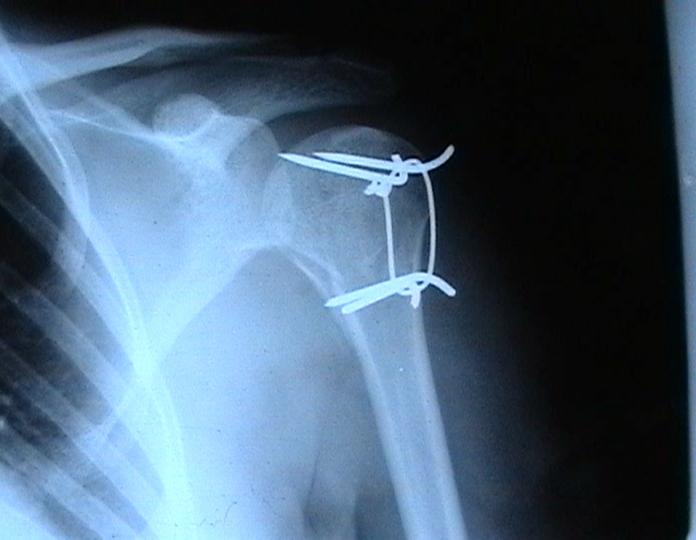

Мужчина 25 лет 16 августа 2002 г. в автоаварии получил перелом шейки плеча (снимок 1); 5 сентября в городской больнице выполнен остеосинтез пластинкой (снимок 2).К настоящему времени попал к нам на разработку ввиду выраженной контрактуры плечевого сустава. В течение последнего месяца беспокоят умеренные боли в области плечевого сустава, усиливающиеся при разработке, еще и торчит край пластинки. Нынешняя рентгенологическаякартина на снимках 3 и 4. Головка плеча уменьшается, сращение сомнительное.Кроме удаления пластинки, что еще на сегодня целесообразно сделать?Заранее спасибо.

Переломовывих плеча сложная проблема и технически не уверен как для коллег, но для меня сколько я не встречался, технически сложно *вытянуть* вывихнутую головку из-под впадины. Последнее время не применяю пластины для фиксации перелома, а использую спицы и проволочную петлю (тем более часто и густо спонгиозные винты не держатся в головке прочно).